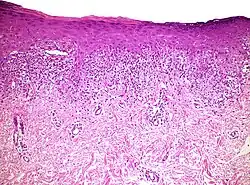

| Histopathology of lichenoid drug reaction. It resembles lichen planus because of irregular epithelial hyperplasia, focal hypergranulosis, orthokeratosis, and a “saw-tooth” pattern of rete ridges. | |

A lichenoid eruption is a skin disease characterized by damage and infiltration between the epidermis and dermis.[1]

Examples include lichen planus, lichen sclerosus and lichen nitidus. It can also be associated with abrasion or drug use.[2] It has been observed in conjunction with the use of proton pump inhibitors, and might be a sign and/or symptom of lupus such as subacute cutaneous lupus erythematous, according to the case reports and reviews.[3][4][5][6]